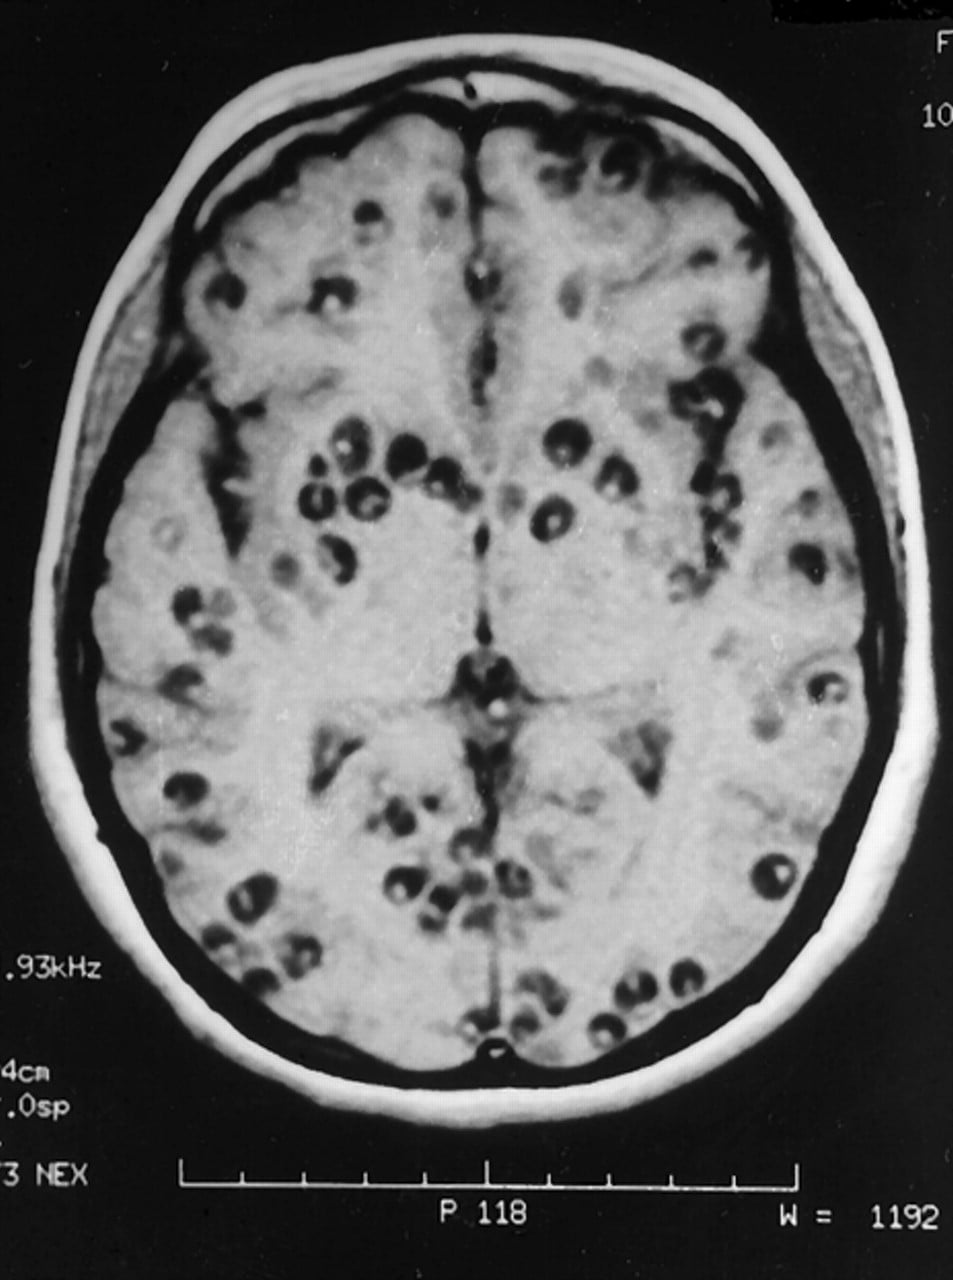

Epidemic disease occurrence level of disease. Disease of the Week: Neurocysticercosis - UCSD Guardian

Disease of the Week: Neurocysticercosis - UCSD Guardian from ucsdguardian.org